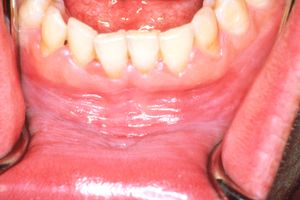

때때로 구강 바닥이나 혀 밑의 백색판증을 "설하 각화증"이라고 부르기도 한다.[23] 그러나 이는 일반적으로 특발성 백색판증과는 구별되는 별개의 임상 실체로 보편적으로 받아들여지지는 않으며,[23] 위치에 의해서만 구분된다.[10] 일반적으로 설하 각화증은 양측성이고 "썰물"이라고 묘사되는 평행 주름진 표면 질감을 가지고 있다.[10]2. 1. 4. 칸디다 백색판증